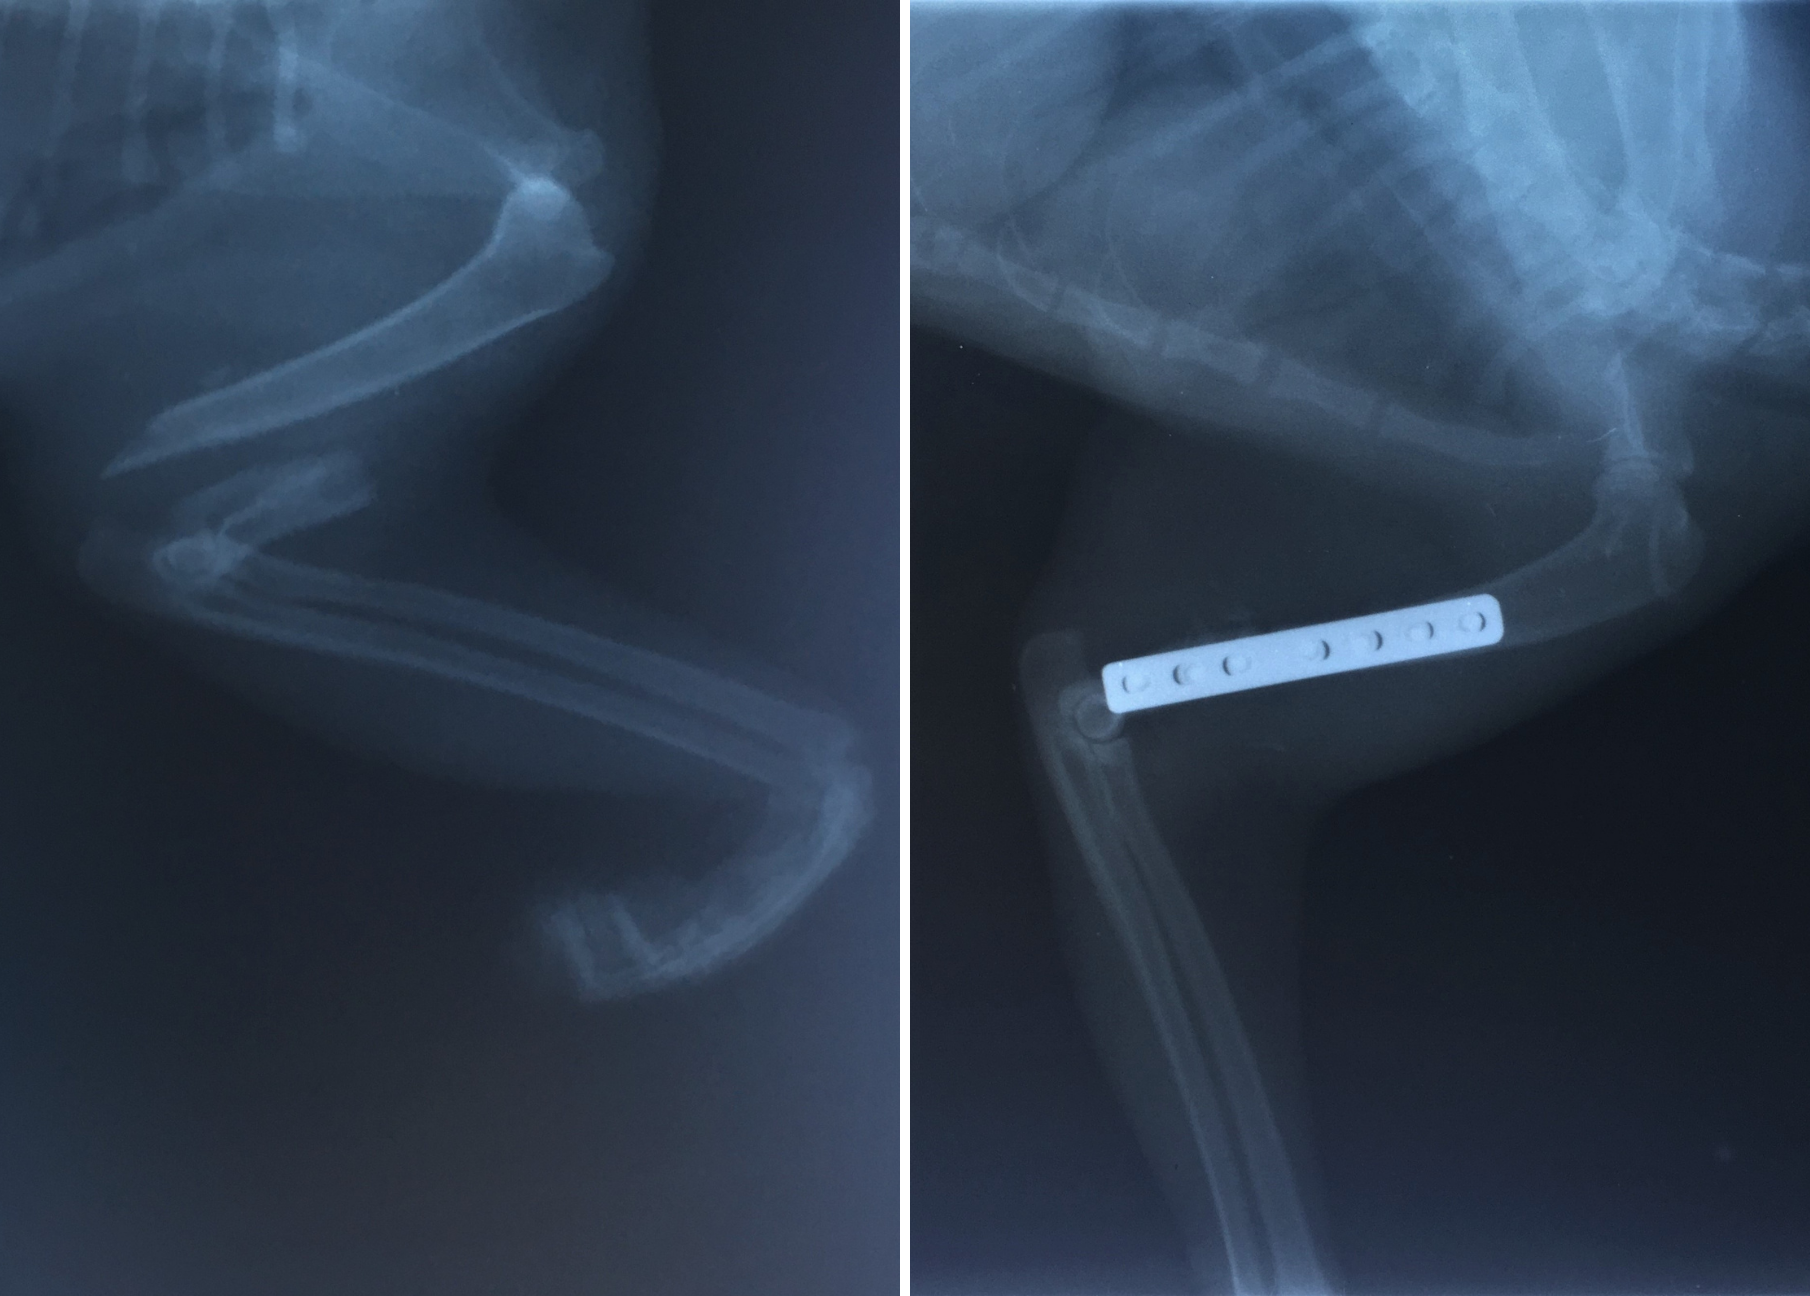

Tomcat with broken shoulder meows for help

The tomcat came to us with a broken shoulder. We have no idea what happened to him, but it surely couldn't have been anything pleasant. 😢 Now the tomcat already underwent a surgery that was truly long and demanding. 😔 So far, he's staying at the vet to be sure, so that the vet could have him under supervision.